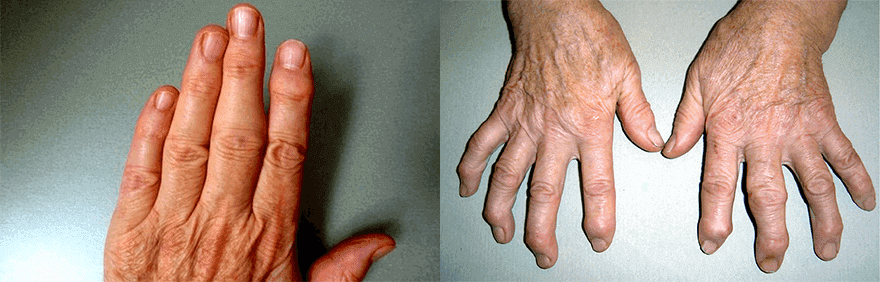

Мен Bioartex крем Хондропротекторидан олдин ва кейин қўлларимни кўрсатаман.

Ўзингиз учун ҳукм қилинг

Худога шукур! Фарқни кўринг: